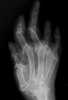

Arthritis mutilans

Arthritis mutilans is a rare medical condition involving severe inflammation damaging the joints of the hands and feet, and resulting in deformation and problems with moving the affected areas; it can also affect the spine. As an uncommon arthropathy, arthritis mutilans was originally described as affecting the hands, feet, fingers, and/or toes, but can refer in general to severe derangement of any joint damaged by arthropathy. [Source: Wikipedia ]